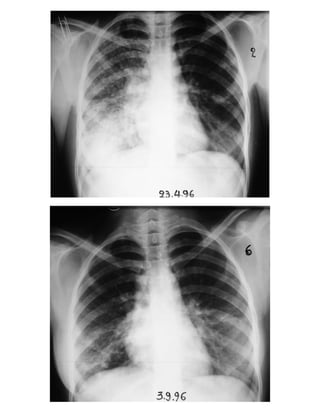

- Περιπτώσεις με επασβαστιωμένη πρωτοπαθή εστία και πρωτοπαθή συμπλέγματα 109

ΦΥΜΑΤΙΩΣΗ

Πρωτοπαθής εστία εν ενεργεία